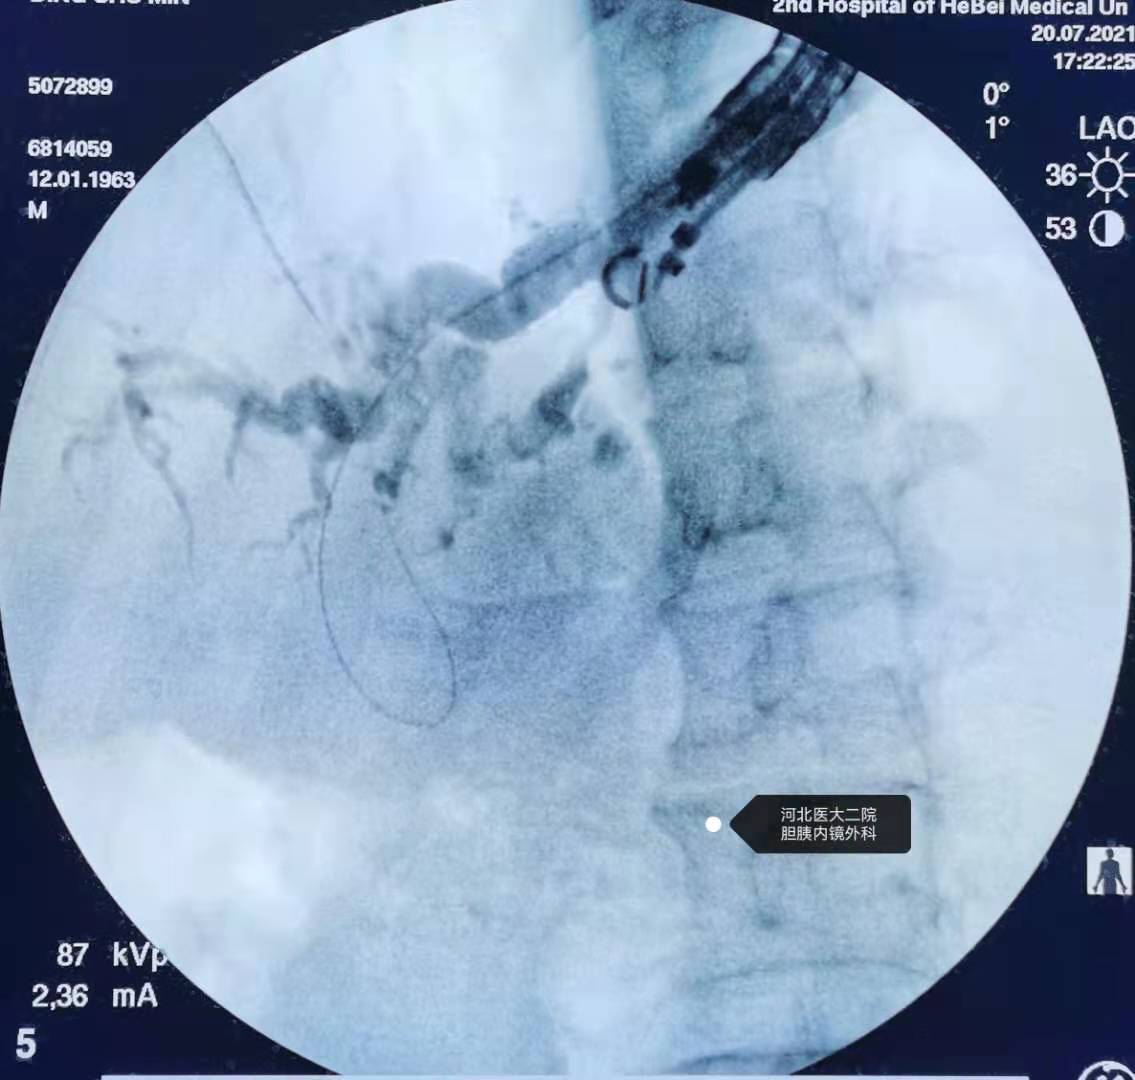

造影。

继续造影。